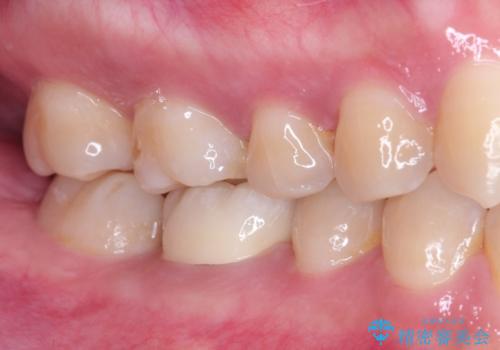

今回の治療では、まず左下6番と7番の欠損部に、骨の状態を考慮しながら慎重に2本のインプラントを埋入しました。インプラント体と骨がしっかりと結合するのを待った後、最短の期間で最終的な被せ物を装着するための精密な型取りを実施。最終的に、周囲の歯と調和した審美性の高いセラミック製の歯を装着しました。

治療期間は約3ヶ月で完了。以前の入れ歯のような煩わしさや動く心配がなくなり、天然歯と変わらない強い力でしっかりと食べ物を噛み砕けるようになり、快適な食生活を取り戻していただけました。